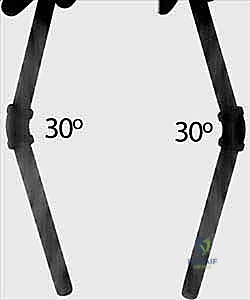

Age-dependent angulation limits are the primary drivers for surgical decision-making. In children under 8 to 10 years of age, greater than 20 degrees of angulation in the distal third, greater than 15 degrees in the central third, and greater than 10 degrees in the proximal third are generally unacceptable. For children over 10 years of age, the tolerance is much lower; generally, no more than 10 degrees of angulation is acceptable at any level due to the diminished remodeling potential. Furthermore, rotational malalignment exceeding 30 to 45 degrees is an absolute indication for correction, as it will not remodel and will result in a permanent mechanical block.

This remodeling potential is most predictable and robust in children under the age of 8 to 10 years. As a child approaches adolescence, the remaining growth potential diminishes, and the tolerance for angular and rotational malalignment drops precipitously. Older children, and those presenting with complete, widely displaced fractures, have much stricter limits for acceptable displacement. Rotational malalignment, in particular, remodels exceptionally poorly at any age and must be anatomically corrected during surgical intervention to prevent permanent deficits in pronation and supination.